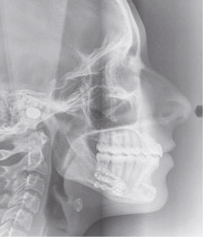

Examen clinique (fig. 1 à 7)

Son visage de face est équilibré et symétrique ; en revanche, au niveau de son profil elle présente une rétromandibulie avec un sillon labio-mentonnier marqué.

À la vue de l’examen radiographique, elle est au stade CS6 d’après la méthode de maturation vertébrale de Baccetti [1]. Elle présente une classe II squelettique de Ballard par rétrognathie mandibulaire avec un ANB de 9° et un AoBo de 9 mm sur un schéma facial normo-divergent. L’incisive mandibulaire est vestibulo-versée (IMPA = 114°). Le maxillaire est bien positionné. Elle présente de plus une dysharmonie dento-dentaire (DDD) antérieure par excès mandibulaire.